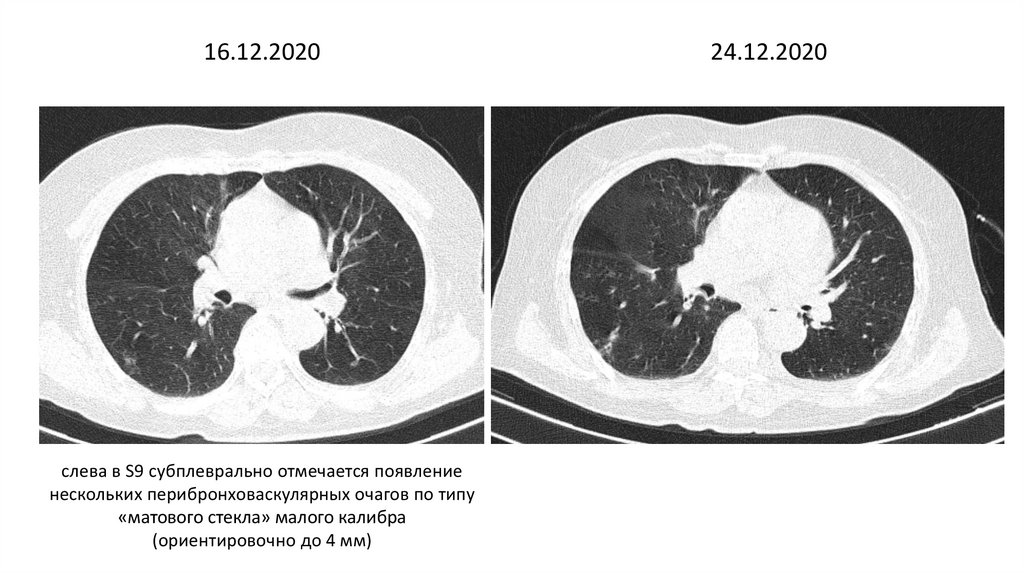

16.12.2020

слева в S9 субплеврально отмечается появление

нескольких перибронховаскулярных очагов по типу

«матового стекла» малого калибра

(ориентировочно до 4 мм)

24.12.2020